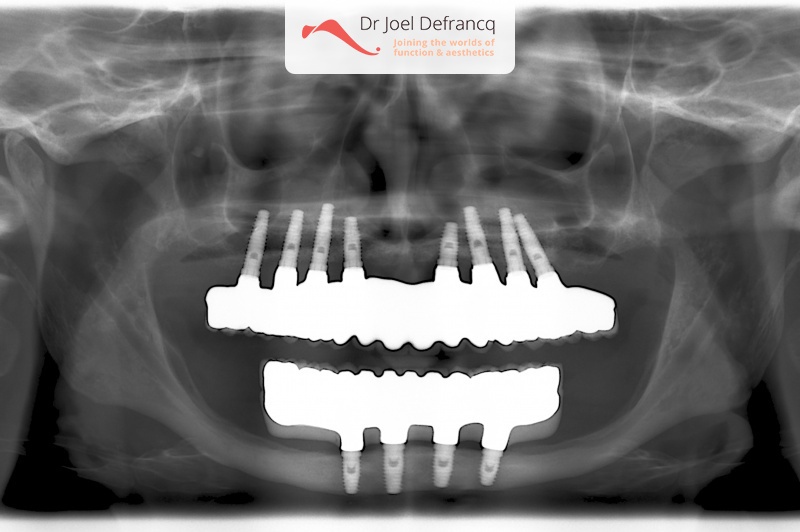

Daphne: from extreme atrophic to fixed teeth on implants

Behandeling tandheelkundige implantaten

- Vaste tanden op implantaten (bovenkaak)

- Vaste tanden op implantaten (onderkaak)

- Implantaten met beenopbouw